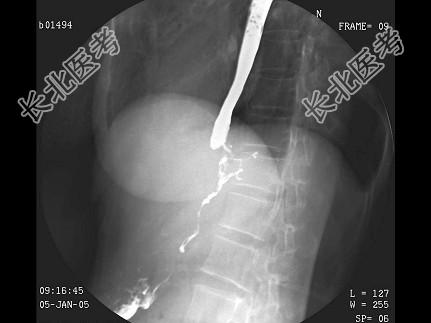

- 单项选择题女,53岁, 进行性吞咽困难伴呕吐,吐黏液半月, 结合图像,最可能的诊断为 ( )

A、食管癌

B、贲门癌

C、食管静脉曲张

D、贲门失弛缓

E、胃底癌